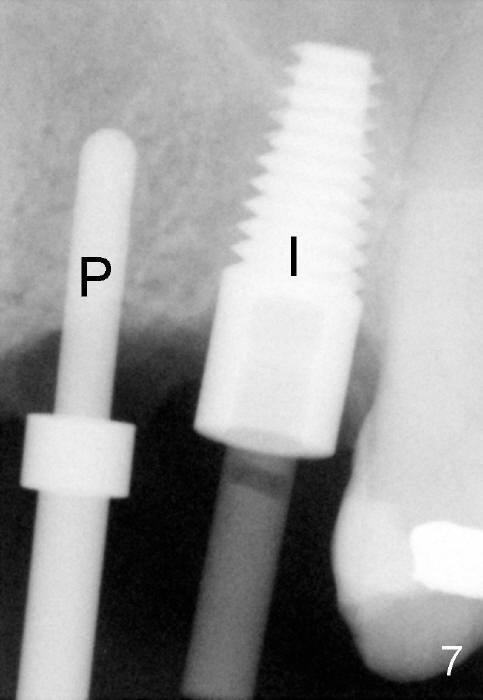

The anterior retainer is kept as a crown at #11 (Fig.2: C), whereas the residual root at the site of #13 is extracted with apical perforation (Fig.3 ^). It is confirmed by Fig.4 (<). To close the perforation, an osteotomy is initiated on the palatal wall of the socket with a 2 mm osteotome (Fig.5 insert: circle). As the osteotomy is being enlarged by a 3 mm osteotome, the bone between the original socket and the osteotomy is being pushed buccally. The former is being closed (Fig.5). The osteotomy is finished with combination of osteotomes and reamers. Fig.6 shows that a 5x14 mm tap is inserted at the site of #13 and that the sinus floor is lifted. In fact the sinus membrane is partially torn at the osteotomy, which is repaired by insertion of Colla-form Dressing (Impladent), followed by autogenous bone (harvested from reamers) mixed with Osteogen (Impladent). A 5x14 mm implant is placed at the site of #13 with insertion torque more than 60 Ncm (Fig.7: I). An incision is made at the site of #12 to start osteotomy with insertion of a parallel pin (Fig.7 P). A 3 mm reamer is kept in place for position confirmation (Fig.8 R). Due to ridge atrophy (Fig.2 arrowheads), a much smaller, but longer implant is placed at the site of #12 (Fig.9: 4x17 mm). The autogenous bone harvested from #12 osteotomy is placed in the buccal gap of #13, followed by insertion of Colla-form Dressing (Fig.10 M). To protect the membrane, a short abutment (4x3 mm) is temporarily placed (Fig.9,10 A) and perio dressing (Fig.9 D) is applied around the abutment and the interproximal areas of the neighboring teeth. Usually perio dressing dislodges around 1 week postop, particularly for a large edentulous space. In this case, the dressing is quite stable 11 days postop: the abutment (Fig.11 A) appears to contribute to retention of the dressing (D).